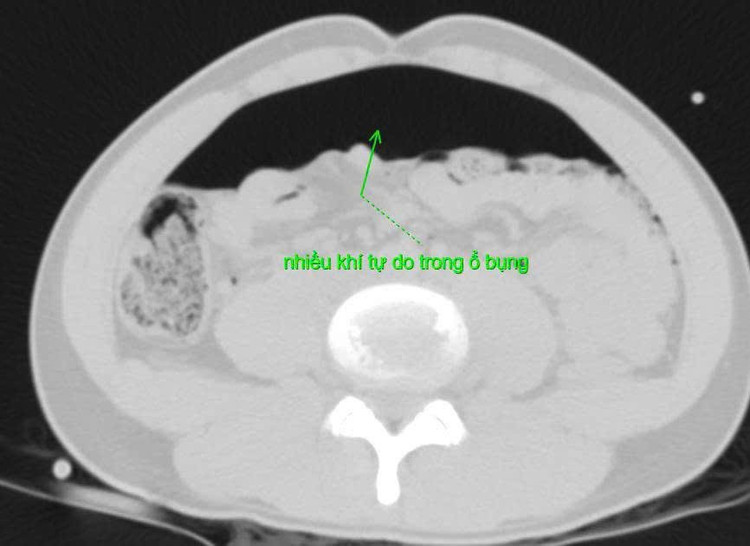

Bệnh nhân nhập viện trong tình trạng đau bụng dữ dội, bụng chướng căng, khó thở và mệt lả. Khai thác bệnh sử ghi nhận trước đó bệnh nhân bị bạn trêu đùa và dùng vòi xịt rửa xe ô tô (áp lực cao) để xịt vào hậu môn. Kết quả chụp X-quang và CT scan ổ bụng cho thấy nhiều khí tự do trong ổ bụng, nghi ngờ thủng tạng rỗng. Bệnh nhân được chỉ định mổ cấp cứu ngay.

Ảnh chụp cắt lớp vi tính ổ bụng/Ảnh BV